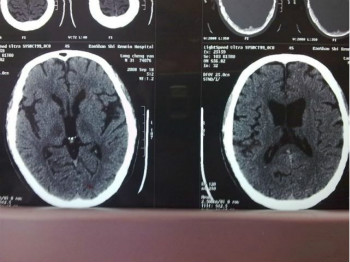

其中錐體系疾病常見于腦梗死、腦出血、腦外傷、脊髓炎、脊髓腫瘤、脊髓血腫等疾病,多表現(xiàn)為肌張力的增高,屬于肌痙攣性的,也就是說屬于痙攣性的肌張力增高,上肢會表現(xiàn)為內(nèi)收肌屈肌以及旋前肌為主的張力增高的現(xiàn)象,出現(xiàn)上肢屈肌和下肢伸肌明顯的肌張力增高現(xiàn)象,被動運動會導致患者的關節(jié)開始時阻力較大。這些疾病診斷、治療較為復雜,均需要有經(jīng)驗的神經(jīng)內(nèi)科醫(yī)師進行。